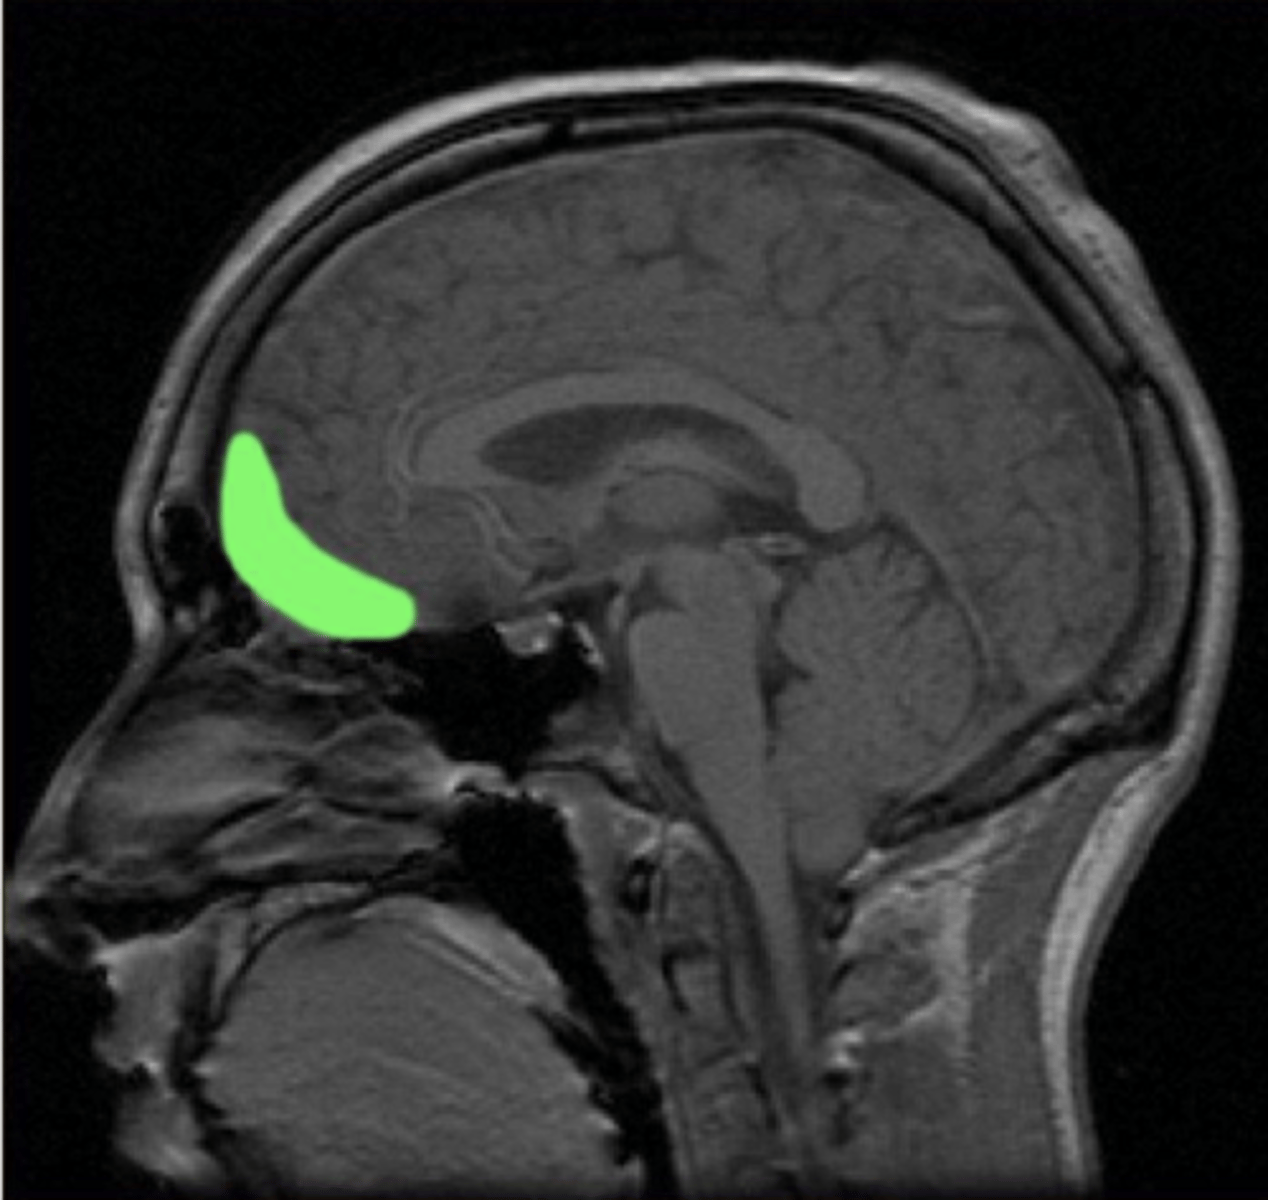

anterior cingulate cortex

orbitofrontal cortex (OFC)

- one of the functional parts of the prefrontal cortex, sometimes called ventromedial

dorsolateral prefrontal cortex (DLPFC)

- one of the functional parts of the prefrontal cortex (scribbled out area)